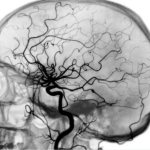

- Stroke

- Traumatic brain injuries

Another thing is damage to the tissues of the nervous system when there is not enough substance in the body. The benefits of amino acids for various brain injuries are undeniable. In particular, glycine is important for children, especially infants, who have postpartum injuries that negatively affect the functioning of the nervous system. There are also studies showing improved sleep as a result of taking glycine preparations.

- helps speed up recovery after strokes;

- Ischemic stroke

For ischemic stroke - 10 tablets under the tongue within 3-6 hours after the stroke, then 10 tablets per day for 5 days, then 3 tablets per day for a month.